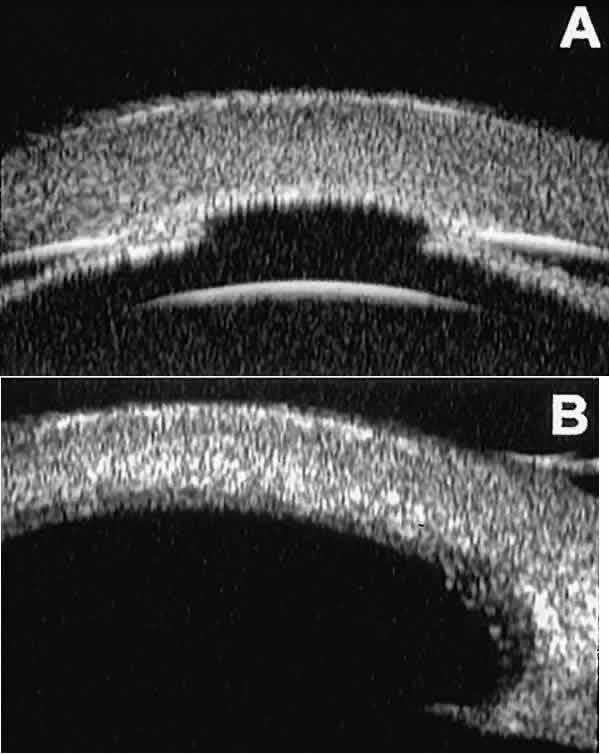

CATARACT AND INTRAOCULAR LENS The role of UBM in the preoperative assessment of eyes with cataract is

as yet unknown. In certain eyes, however, UBM may reveal features or

abnormalities that could alter the ophthalmologist's surgical approach. Postoperatively, UBM can show the size and location of an intraocular

lens (IOL) and the positioning of the haptics. A posterior chamber

IOL appears on UBM as a highly reflective plate (corresponding to

the lens optic) in the retropupillary plane with reverberation artifacts

behind it (Fig. 17A). In contrast, an anterior chamber IOL appears on UBM as a sonoreflective

plate located anterior to the pupillary plane (see Fig. 17B). In most eyes with a posterior chamber IOL, UBM can show whether the

haptics are in the capsular bag (Fig. 18A), in the ciliary sulcus (see Fig. 18B), or in some other anatomic location12 (e.g., resting on the peripheral iris or secured with sutures to the sclera). The

haptics are easier to locate if they are made of polymethyl-methacrylate

than if they are made of proline because the former has a stronger

reflectance.  Fig. 17. Composite UBM images of intraocular lenses. A. Posterior chamber IOL. B. Anterior chamber IOL. Fig. 17. Composite UBM images of intraocular lenses. A. Posterior chamber IOL. B. Anterior chamber IOL.

|

Fig. 18 . Localization of posterior chamber IOL haptics by UBM. A. Haptic in capsular bag (arrow). B. Haptic (bright object just behind peripheral iris) in iridociliary sulcus. Fig. 18 . Localization of posterior chamber IOL haptics by UBM. A. Haptic in capsular bag (arrow). B. Haptic (bright object just behind peripheral iris) in iridociliary sulcus.

|

Ultrasound biomicroscopy appears to be helpful postoperatively in determining

the extent of postoperative complications of cataract surgery such

as serous choroidal detachment (see Fig. 13A), iridocapsular adhesion (Fig. 19A), postoperative hyphema (see Fig. 19B), stripping of Descemet's membrane (see Fig. 19C), and wound gaping (see Fig. 19D).  Fig. 19. Complications of cataract surgery revealed by UBM. A. Capsular adhesion to midzone of iris. B. Postoperative hyphema. Clot appears denser than aqueous with suspended

blood cells. C. Stripping of Descemet's membrane. D. Wound gape. Fig. 19. Complications of cataract surgery revealed by UBM. A. Capsular adhesion to midzone of iris. B. Postoperative hyphema. Clot appears denser than aqueous with suspended

blood cells. C. Stripping of Descemet's membrane. D. Wound gape.

|